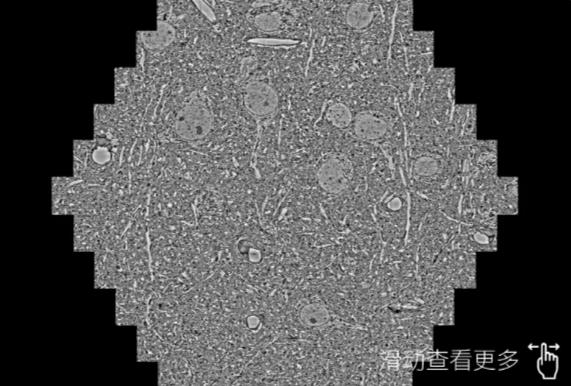

鼠脑切片。左图使用西青蔡司西青扫描电镜MultiSEM706对165μmx143pm面积区域成像,耗时仅需1.5秒。右图为鼠脑切片中30μm区域放大效果。样品由芝加哥大学B.Kasthuri提供。

使用蔡司高速西青扫描电镜MultiSEM对1mm²人脑皮层组织进行高分辨成像,并对其中的各种细胞结构进行三维重构分析。左图展示了2x3mm²组织平面中锥体神经元的三维重构效果。右图显示了局部体积神经元三维重构。图像由哈佛大学chtman实验室提供,渲染图由D. Berger 制作。